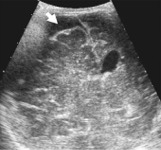

Рисунок 4. Тот же ребенок, осмотр

через 1 месяц после травмы.

|

|

|

| а - нейросонография, В-режим, правая парасагиттальная плоскость. Определяется

резкая дилятация визуализируемых фрагментов бокового желудочка, структура мозговой

ткани нарушена |

б - то же, фрагмент. Определяется деструкция мозговой ткани с образованием

множественных кистозных полостей мелких размеров (энцефаломаляция) |

в - тот же ребенок, фронтальная плоскость сканирования. Очаги энцефаломаляции

определяются в обоих полушариях |

г

- допплерография на средней мозговой артерии - показатели периферического сопро-тивления

в пределах возрастной нормы. г

- допплерография на средней мозговой артерии - показатели периферического сопро-тивления

в пределах возрастной нормы. |